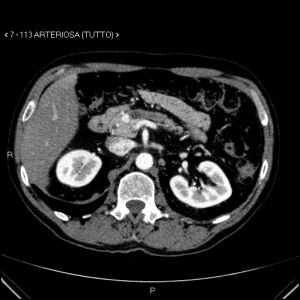

image

Aspetti TC: piccolo nodulo istmico ipervascolarizzato in fase pancreatica